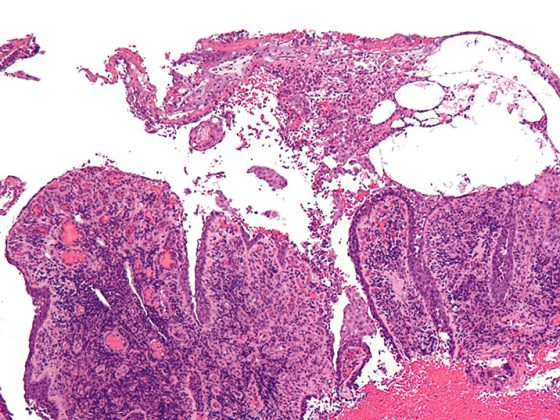

pemphigus_vulgaris_-_low_mag

CAR-T für Pemphigus vulgaris als zukünftige Therapieoption?